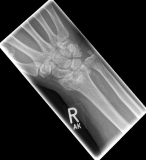

Often the inspection of the wrist already shows a suspected diagnosis. The accident mechanism must be clarified and after the physical examination, X-ray images of the wrist must be made in 2 levels.

In the classification of the distal radius fractures, the position of the fracture as well as a possible involvement of the articular surface are considered. Furthermore, the accident mechanism allows a classification of the fractures: the fall on the outstretched hand leads to a so-called extension fracture (Colles fracture), while the fall on the bent hand leads to a flexion fracture (Smith fracture).